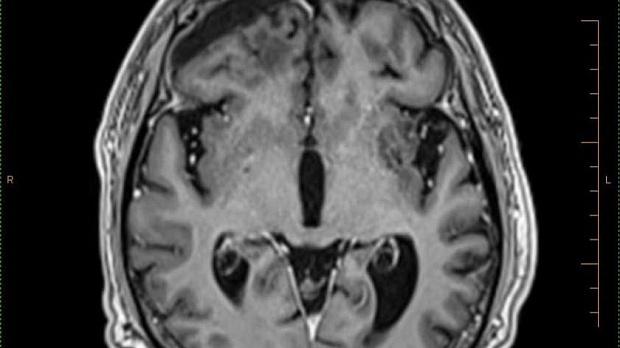

Иллюстрация №2: Рис. 2. Опухолевый очаг в левой височной доле размерами 36 х 25 мм.

По данным МРТ головного мозга от 21.03.2018г. отмечалась отрицательная динамика в виде увеличения размеров образования в левой височной доле до 36 х 25 мм, увеличения перифокального отека (рис. 2).